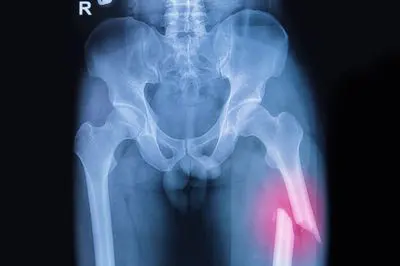

Déjà , qu’est-ce que le fémur ? Le fémur c’est l’os unique de la cuisse. Il est le plus long, le plus gros et le plus fort de tous les os. Il représente environ un quart de la hauteur du corps et peut supporter des pressions très élevées (jusqu’à 280 kg/cm2 lors d’un saut). Il est situé entre l’os du bassin et le genou.

Les signes cliniques sont une douleur très exacerbée. Il n’est plus possible de marcher. Dans tous les cas, on constate l’impossibilité du patient de mobiliser son membre inférieur. On observe aussi parfois une déformation, la cuisse est souvent raccourcie et elle-même augmentée de volume. Le diagnostic de confirmation se fera grâce à une radiographie.

Quant au traitement, il est quasi toujours chirurgical. Par contre en fonction de la complexité, la méthode thérapeutique sera différente. S’il s’agit d’une conséquence à une chute et non d’usure prématurée l’ostéosynthèse est souvent de rigueur. Celle-ci consiste en une réparation de la fracture par la pose d’une vis-plaque ou de plusieurs vis pour stabiliser la fracture, qui se consolidera ensuite toute seule en deux mois environ.

Les fractures du fémur ne sont donc pas si rares chez les cyclistes. Cependant il faut dissocier les fractures de la diaphyse fémorale (longue partie de l’os) de celles du col du fémur. Les fractures de la diaphyse surviennent en général dans un contexte traumatique de chute. Alors que les fractures du col surviennent préférentiellement dans un contexte d’ostéoporose qui rend les os plus fragiles. L’extrémité supérieure du fémur, qui comprend le col et la tête, est très exposée à l’ostéoporose ce qui la place en haut du palmarès des fractures chez les « anciens ».Â